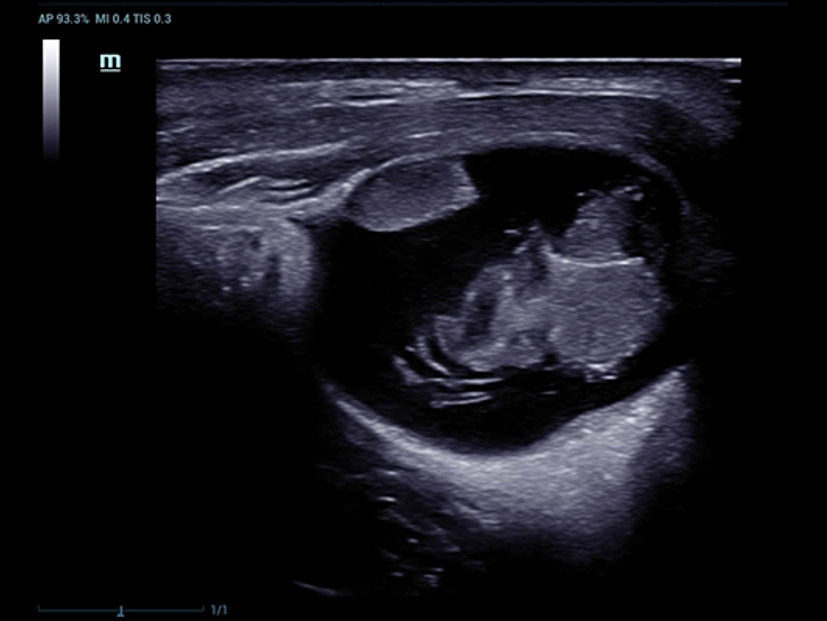

Desde que se fund├│ la compa?├Ła, Mindray ha explorado incansablemente nuevas formas de mejorar la confiabilidad del diagn├│stico. Con la revolucionaria tecnolog├Ła de ZONE Sonography?, la nueva plataforma ZST+ de Resona?7 lleva la calidad de la imagen por ecograf├Ła a un nivel superior mediante el procesamiento de datos de canal y la adquisici├│n de zona.

Adem├Īs de la calidad de imagen de primer nivel, Resona?7 tambi├®n mejora las capacidades de investigaci├│n cl├Łnica con el revolucionario V?Flow para la evaluaci├│n hemodin├Īmica vascular y con la adquisici├│n de planos m├Īs inteligente a partir de conjuntos de datos 3D para el diagn├│stico del SNC fetal. Al combinar el funcionamiento multit├Īctil basado en gestos m├Īs intuitivo y todas las caracter├Łsticas cl├Łnicas esenciales, Resona?7 realmente lidera las novedades en innovaci├│n de ecograf├Łas.